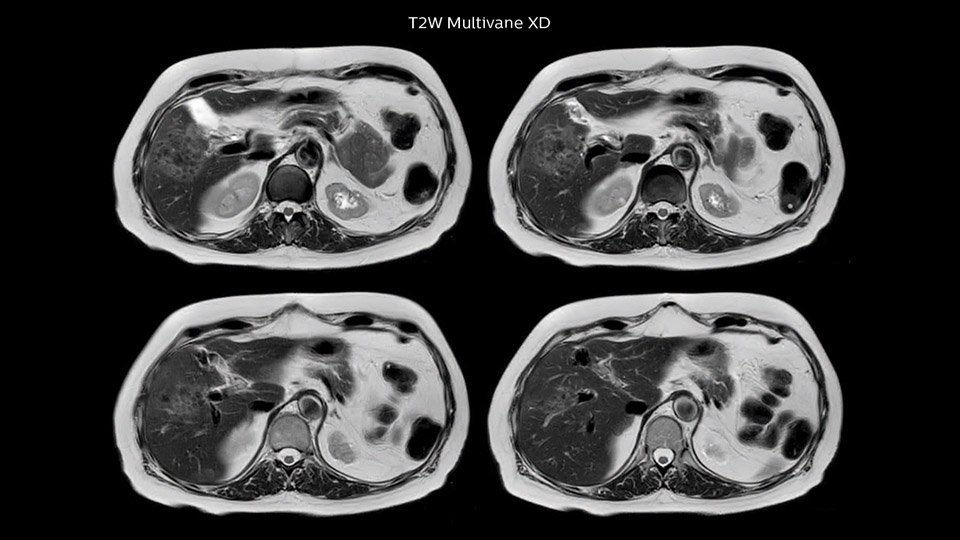

In this example the image quality of the MultiVane XD images is evidently better than in the images without MultiVane XD. Ingenia 1.5T with dS Torso coil solution.

Dr. Baumann then implemented MultiVane XD for motion correction. It uses an extended reconstruction algorithm for imaging that is virtually motion free. “With MultiVane XD we get excellent motion-corrected images with high spatial resolution. We typically first optimize our scan for high image quality, and when satisfied with that, we try to reduce the scan time. So, we combined MultiVane XD with dS SENSE, which allows us to shorten the scan time,” he explains. “The performance of MultiVane XD in liver imaging is outstanding. MultiVane XD with dS SENSE is a powerful development in improving liver image quality.” “As we use breathhold imaging for T2-weighted liver scans, we depend on the patient’s ability to cooperate with the exam. This can present a real challenge when we are looking for small lesions, such as in our oncological patients. However, with MultiVane XD motion correction, we get excellent images. This is important for our surgeons, because they want to know exactly where the lesions are.”

“Our liver exams are quite fast,” says Dr. Baumann. “If the patient tolerates it, we use an arms-up position to reduce the FOV and speed up the exam with dS SENSE.” “We acquire one transversal high resolution T2-weighted sequence with 3 mm slice thickness, for example for pancreas or liver lesions. Then we also add a T2 fat suppressed MultiVane XD SPIR sequence. We perform these two routinely in our liver imaging. We use high dS SENSE factors to significantly shorten scan times to 2-4 minutes, which can improve our protocol; it’s a very robust scan.” “We include mDIXON for the dynamic sequences because of the robust and homogeneous fat suppression we get with that. We had been using eTHRIVE, but we are now quite happy with mDIXON. Sometimes we use a medication to calm the bowels, to further improve the image quality.”